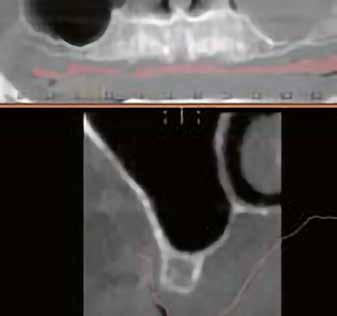

A-PRF membránokkal borítottuk (7. ábra). A mukogingivális lebenyt – annak megnyújtása nélkül – a helyére fektettük és varratokkal rögzítettük, per primam sebzárást nem végeztünk (8., 9. ábra). A varratokat 2 hét után távolítottuk el, a varratszedésig a sebgyógyulás támogatására per os 1000 mg/nap C- és 12 000 NE/nap D-vitamint adtunk (20). A műtéti beavatkozást 24 hét gyógyulási időszak követte, melynek során sem helyi, sem gyógyszeres kezelés nem történt, az esztétikum javítása érdekében a páciens ideiglenes kivehető fogpótlást használt. A csontos gyógyulás ellenőrzése és az implantáció tervezése céljából állcsonti CT felvételt készítettünk, illetve lenyomatvételt végeztünk. A CT felvételen tökéletes csontos gyógyulást észleltünk, az alveolaris csont volumene teljes mértékben megtartott volt (10. ábra), a klinikai kép is ennek megfelelően alakult (11., 12. ábra)

A Trishape Implant Studio™ a korábbi csont augmentáció területén, a felső állcsontnál áltagosnak számító D2-D3 csontminőséget jelzett (13. ábra). A lenyomat alapján készített gipszmodellt szkennelve virtuális mintát nyertünk. A CBCT felvétel és a virtuális modell adatait a Dual Scan protokoll (21) elveinek megfelelően használtuk fel az implantációs sablon (New Age Dental Kft, Nemeskéry Károly) készítéséhez (14., 15., 16. ábra). Az implantátum (Ankylos C/X A11) behelyezése teljesen navigált módon, 35 Ncm primer stabilitással történt (17., 18. ábra). Az implantátumra a fogtechnikus (D1 Dental Kft., Garamvári Csaba) által előzetesen